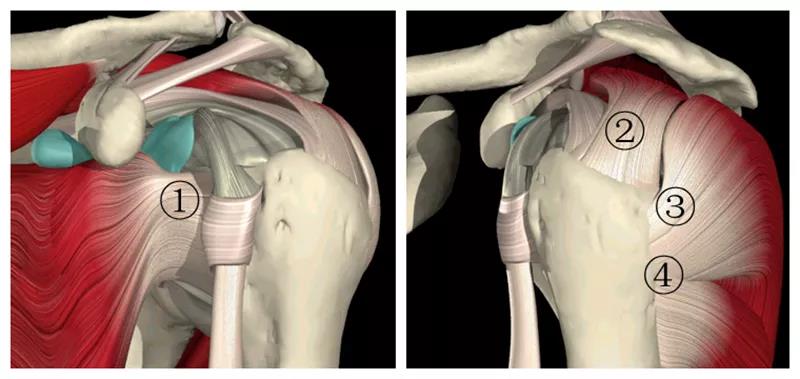

肩袖是由冈上肌、冈下肌、肩胛下肌及小圆肌的腱性部分组成的鞘状结构。它包绕盂肱关节、肱骨头、关节囊,形成近似袖套样肌样结构,具有保持肱盂关节稳定,维持上臂各种姿势和完成各种运动的功能。

图2 肩袖解剖 1.肩胛下肌 2.冈上肌 3.冈下肌 4.小圆肌